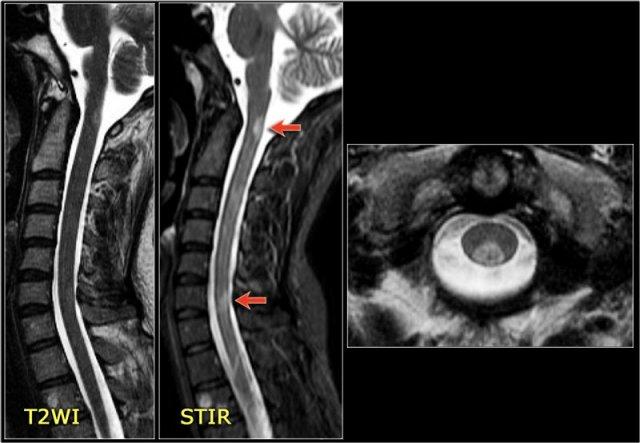

Viêm Tủy Thị Thần Kinh (Neuromyelitis Optica)

NMO biểu hiện với viêm thần kinh thị giác (mũi tên). Não bình thường. Hình ảnh cung cấp bởi Andrea Rossi

Hình ảnh bên trái của một trẻ em nhập viện với viêm thần kinh thị giác một bên.

Hình ảnh não hoàn toàn bình thường.

Tiếp tục xem MRI cột sống.

Những bệnh nhân có một đợt viêm thần kinh thị giác hoặc viêm tủy và có kết quả xét nghiệm NMO-IgG dương tính có nguy cơ cao tiến triển thành toàn bộ phổ bệnh NMO.

Một tháng sau, trẻ này nhập viện với bệnh tủy cắt ngang cấp tính, tức là các triệu chứng hai bên.

Hình ảnh cho thấy tín hiệu bất thường trong tủy sống kèm phù nề và ngấm thuốc nhẹ.

U tế bào hình sao (astrocytoma) hoàn toàn có thể biểu hiện với hình ảnh tương tự, tuy nhiên dựa vào tiền sử viêm thần kinh thị giác và bệnh tủy cấp tính, chúng ta không nghĩ đến khối u.

Trường hợp này được xác định là NMO và xét nghiệm Ig cho NMO dương tính.